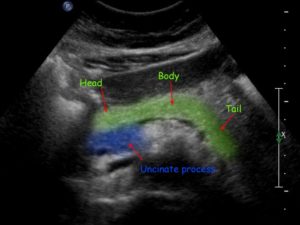

Основными частями поджелудочной железы является головка, тело посередине и хвост, в крайнем левом углу. Самая длинная часть поджелудочной железы расположена слева от средней линии, а хвост около селезеночной мышцы обычно слегка над головкой.

Достаточно сложная форма поджелудочной железы и ее близкое расположение к близлежащим структурам может затруднить ее распознавание, но опытные врачи ультразвуковой диагностики умеют использовать окружающие структуры для определения некоторых границ поджелудочной железы.

Например, голова и тело поджелудочной железы расположены ниже печени, перед нижней полой веной и аортой, обычно расположены за дистальной частью желудка. В крайнем левом углу хвост поджелудочной железы располагается ниже селезенки и, соответственно, над левой почкой.